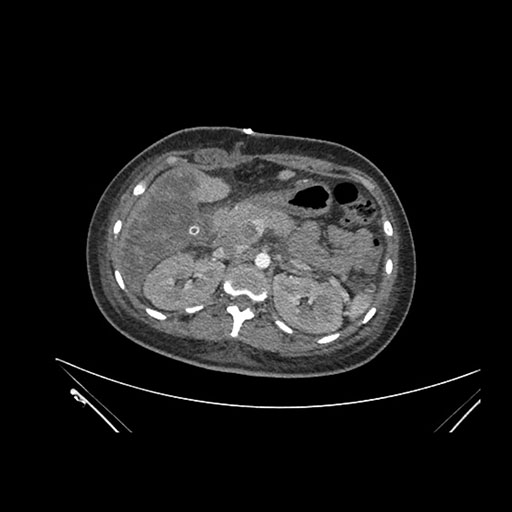

Imaging Analysis

Look through the patient's CT scan to identify any areas of concern for the necessary procedure.

Coronal Venous

Based on initial findings, which issue(s) would you be most concerned about?